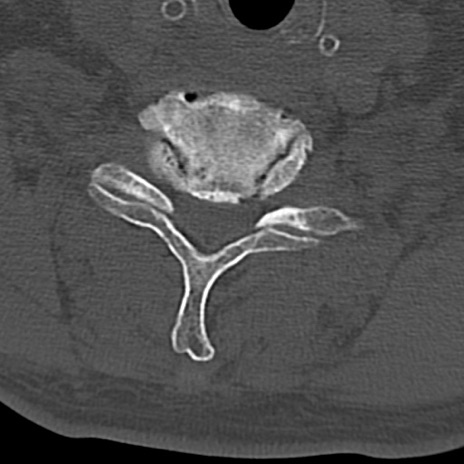

頚椎CT

横断像